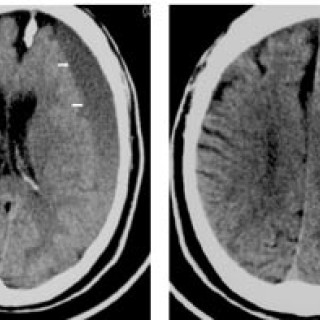

En 52 år gammel etnisk norsk mann ble innlagt i psykiatrisk akuttavdeling etter noen få uker med kraftig økende aktivitetsnivå. Han hadde vist markant endret atferd – blant annet hadde han satt seg fore å sykle åtte mil i kuldegrader og slaps. Ved innleggelsen var han irritabel og snakket fort og nærmest usammenhengende. Somatisk status presens ved innkomst samt orienterende nevrologisk status var normale. Vanlige blodprøver ved innleggelse, inklusive Hb, SR, hvite blodceller, kreatinin, natrium, kalium, ALAT, ASAT, ferritin, folat, kobalamin, FT4, TSH, var alle innenfor referanseområdet...